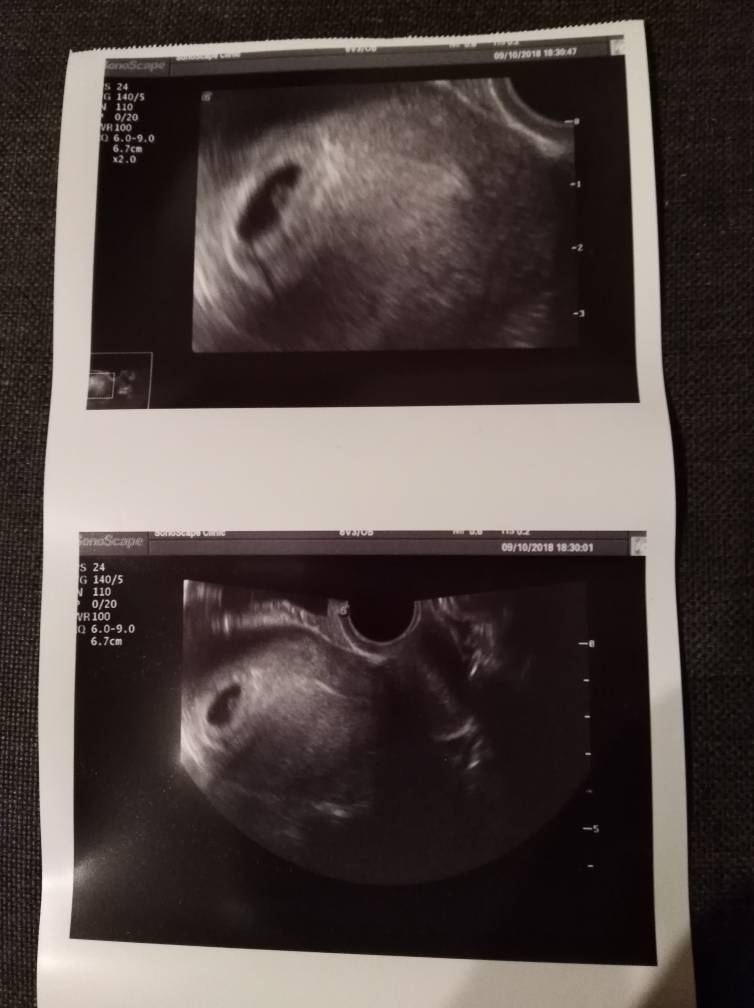

Jestem po wizycie. Na szczęście wszystko jest w porządku. Pan doktor widział tętno płodu, ale jak to on powiedział ciąża jest jeszcze za młoda i serduszko jeszcze jest malutką komórką. Kolejna wizyta miała być 23 października, ale akurat tego dnia jesteśmy z Zuzią w Łodzi u laryngologa, więc wizyta 6 listopada. 22 listopada badania prenatalne.

Załączniki